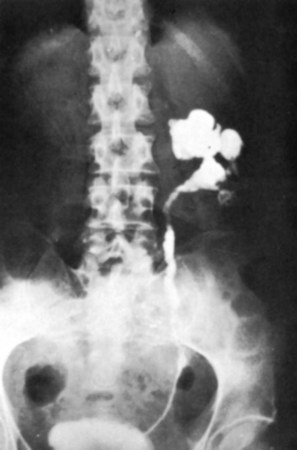

The most common findings on contrast-enhanced CT include renal parenchymal masses and scarring, thick urinary tract walls (ureter and bladder) and extraurinary tubercular manifestations particularly in miliary TB (Wang et al, 2003). Coalescence of caseating granulomata may lead to a renal mass (tuberculoma), which must be differentiated from renal cell carcinoma. CT allows for evaluation of renal function, grading of hydronephrosis and parenchymal scarring (Fig. 16–6). CT is most sensitive in detecting renal calcifications (Premkumar, et al, 1987). Most CT findings are in themselves nonspecific, and the collective interpretation of multiple findings in conjunction with the clinical picture is the best option in decision making (Wang et al, 2003).

Figure 16–6 CT after oral contrast medium in a patient with bilateral tuberculosis. The right kidney is hydronephrotic secondary to infundibular stenosis but has retained good function. The left kidney is an end-stage nonfunctioning atrophic kidney with calcification.